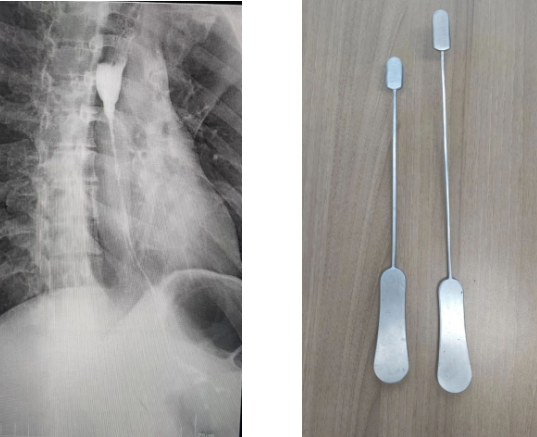

為了建立胸骨后的人工隧道,李小飛教授還自制了一把特殊的彎鉗,用于做胸骨后隧道便于將結腸順利從腹腔經過胸骨后隧道提至頸部。